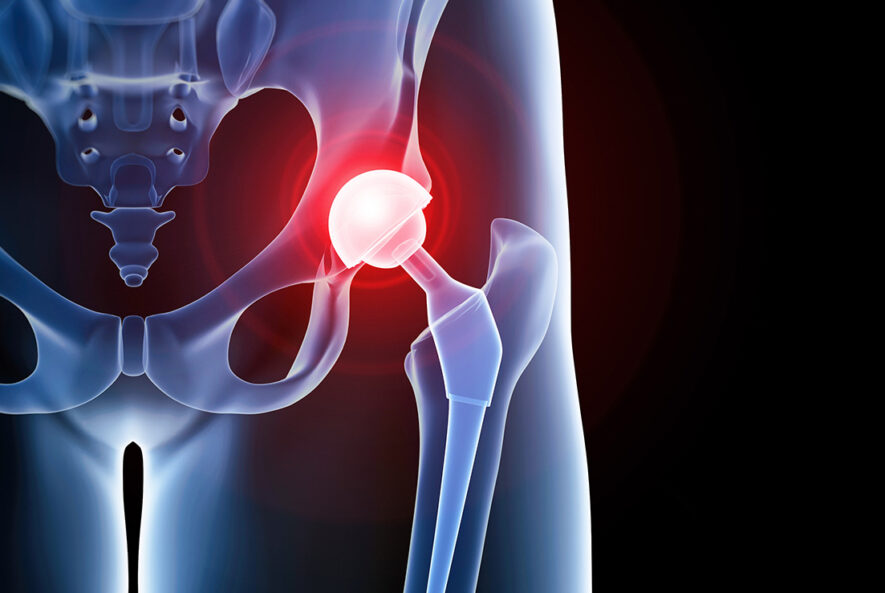

Hasar görmüş kalça ekleminin yapay bir protez ile değiştirilmesi işlemidir. Titanyum, seramik gibi biyouyumlu malzemelerden üretilen protezler, eklem hareketlerini rahatlatır. Hastanın ağrısız bir şekilde yürümesini sağlar. Ameliyatın temel amacı, hareket kısıtlılığını ortadan kaldırarak hastanın yaşam kalitesini artırmaktır.

Ameliyat öncesinde hastanın genel sağlık durumu değerlendirilir ve gerekli tetkikler yapılır. Kan testleri, röntgen, MR ve EKG gibi testlerle hastanın ameliyata uygun olup olmadığı belirlenir. Kalça protezi ameliyatı genellikle genel veya spinal anestezi altında yapılır. Cerrah, hasarlı kalça eklemini çıkararak yerine uygun boyutta bir protez yerleştirir. Bu işlem yaklaşık 1-2 saat sürer. Protezin kemiğe sabitlenmesi çimentolu veya çimentosuz yöntemlerle yapılabilir. Ameliyat sonrası hastalar genellikle 2-5 gün hastanede kalır. İlk günlerde hafif hareketlerle rehabilitasyona başlanır. Hasta, fizik tedavi uzmanları eşliğinde yürümeye teşvik edilir.